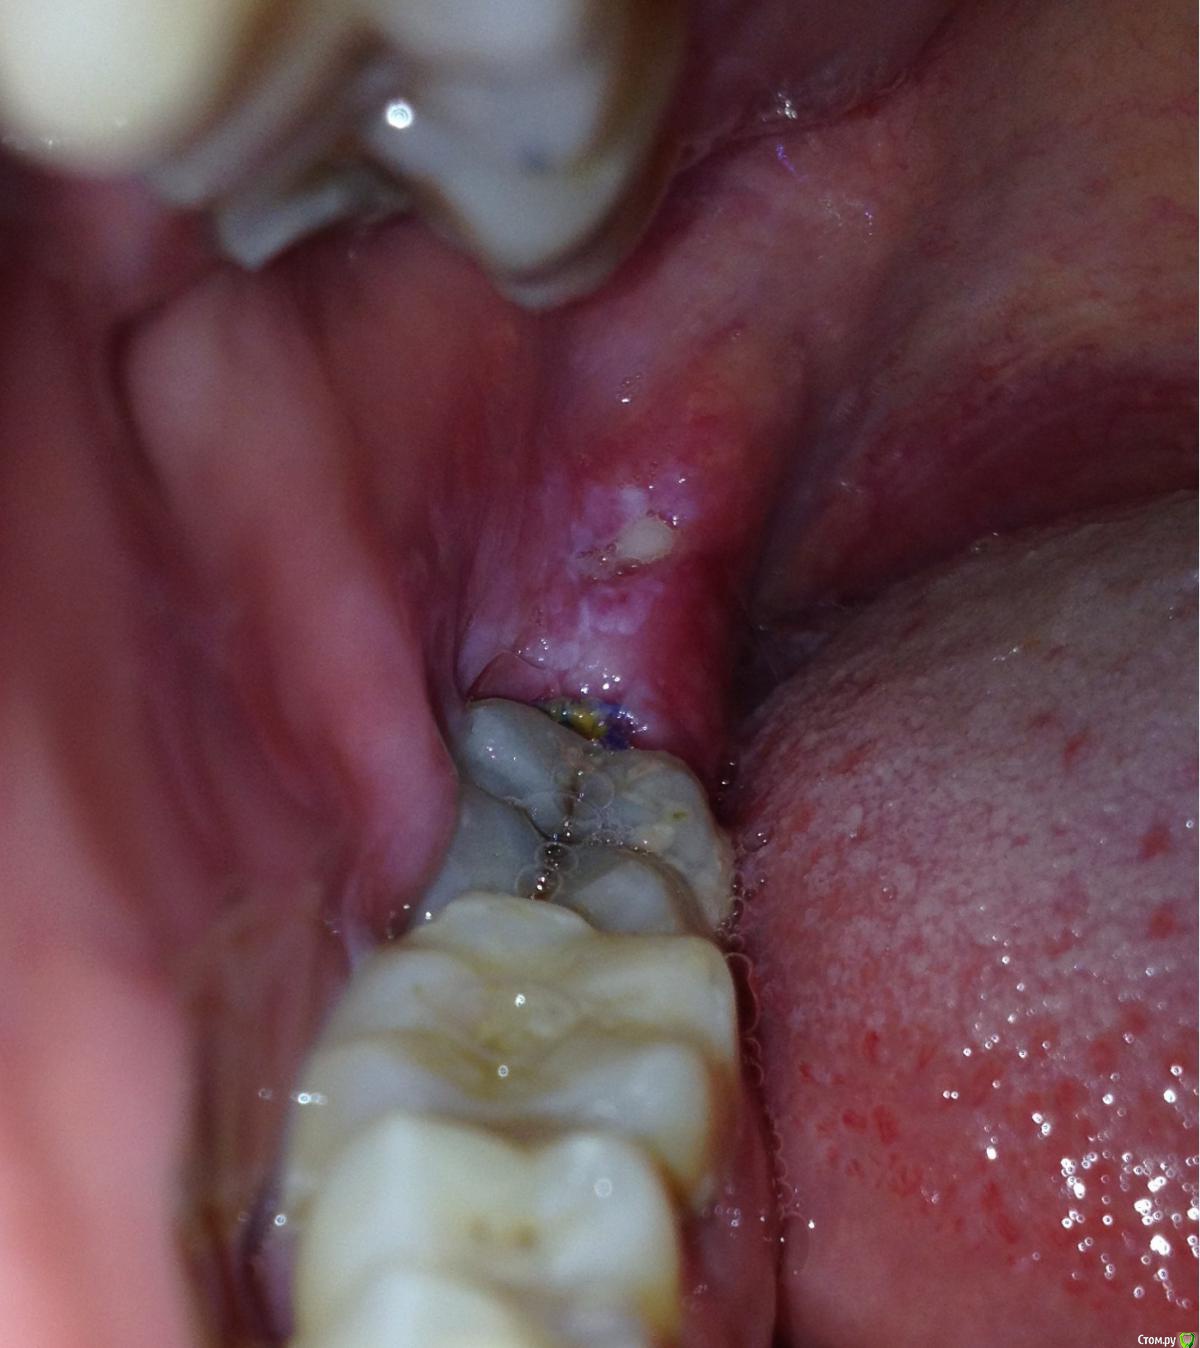

vano-box Опубликовано 10 сентября, 2016 Автор Поделиться Опубликовано 10 сентября, 2016 Доброй ночи. Мажу метрогилом, но пока как то без улучшений, уже 10 день после удаления, а ноет всё равно, разве должно так долго болеть? Сегодня сделал фото лунки, и сделал ортопанораму, скажите там всё нормально?И ещё если трогать щеку беспокоит твердая болезненная гематома, сколько она заживает в среднем? Ссылка на комментарий

red_butler Опубликовано 11 сентября, 2016 Поделиться Опубликовано 11 сентября, 2016 а ноет всё равно, разве должно так долго болеть? а как болит? На семерке похоже пульпит.за операционной областью или стоматит или оголенная кость, попробуйте попасть к другому врачу Ссылка на комментарий

vano-box Опубликовано 11 сентября, 2016 Автор Поделиться Опубликовано 11 сентября, 2016 а как болит? Спасибо большое Вам за внимание к мой теме, боль у меня ноющая, по интенсивности средняя (или чуть ниже среднего), без конкретной локализации, сами зубы вроде не болят, ноет где то внутри челюсти, временами может успокоиться - это в состоянии покоя. А если сжать зубы или широко открыть рот, то волной отдает в гематому, так же если нажать на гематому пальцем она болезненна в одной точке. Вообще из за этой гематомы у меня чувство как будто конфетку за щекой держу, она как то распирает. Когда чищу зубы сверху всё комфортно, а вот если просунуть щетку между щекой и челюстью чувство как будто там воспалена десна, там у меня ещё остался узелок шовного материала, все остальные нитки уже отвалились. Если принять Кетонал, то все быстро проходит на 12 часов. Уфф..., вроде всё описал. Ссылка на комментарий

red_butler Опубликовано 11 сентября, 2016 Поделиться Опубликовано 11 сентября, 2016 нужен очный осмотр, возможно потребуются перевязки.сходите к кому нибудь из врачей форума на осмотр http://forum.stom.ru/topic/16116-posovetujte-khirurgaimplantologa/ Ссылка на комментарий